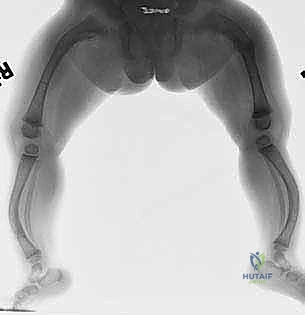

مع مرور الوقت والكسور الدقيقة المتكررة، تبدأ هذه العظام في الانحناء والتقوس (Bowing Deformities). هذا الانحناء يغير من الميكانيكا الحيوية للمفاصل (الركبة والورك)، مما يسبب ألماً مزمناً، وصعوبة في المشي، وفي النهاية قد يؤدي إلى فقدان القدرة على الحركة تماماً إذا لم يتم التدخل الجراحي المناسب.

كان عمار يعاني من النوع الثالث من تخلّق العظم الناقص، مع تقوس شديد في عظمي الفخذين (بشكل حرف O) منعه من المشي تماماً، وجعله حبيس الكرسي المتحرك، مع تاريخ من 8 كسور سابقة. تم إجراء عملية بضع العظم المتعدد عبر الجلد وتركيب مسامير فاسييه-دوفال التلسكوبية في كلتا الساقين في جلسة جراحية واحدة بواسطة الدكتور هطيف. اليوم، وبعد 6 أشهر من الجراحة، يمشي عمار مستقلاً لأول مرة في حياته، ولم يتعرض لأي كسر جديد.

حالة الطفلة "رؤى" (5 سنوات):

عانت رؤى من كسور متكررة في عظم القصبة (الساق) بمجرد محاولتها الجري. أظهرت الأشعة هشاشة شديدة وتقوساً أمامياً. بعد استشارة الأستاذ الدكتور محمد هطيف، تقرر إجراء التدخل الجراحي المحدود. تم تصحيح التقوس بنجاح باهر، وبفضل المسمار التلسكوبي الذي ينمو معها، عادت رؤى للعب مع أقرانها بثقة وأمان.